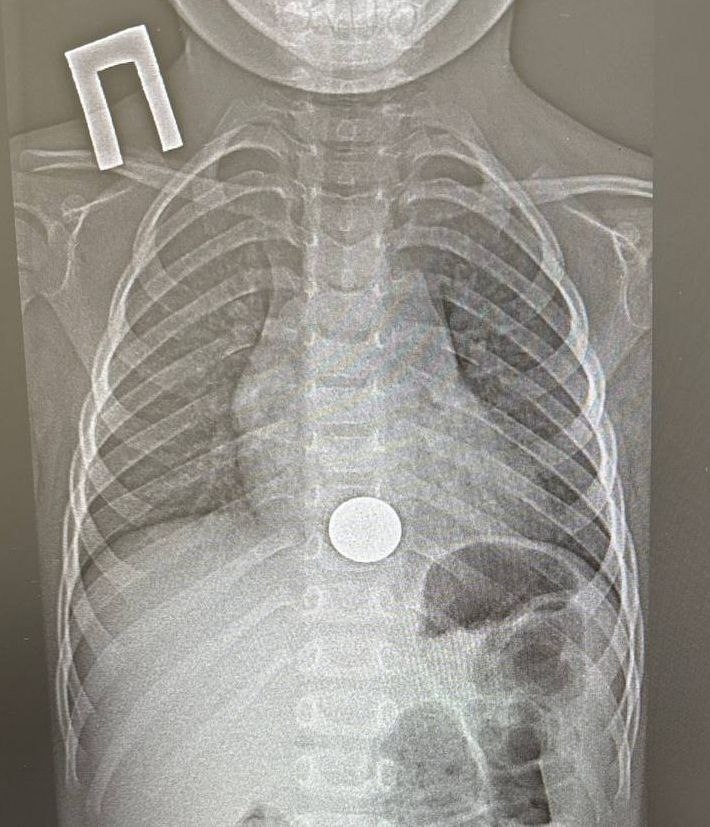

Ребенок поступил в больницу с жалобами на боли за грудиной. Как выяснилось, мальчик взял поиграть монету у старшего брата и случайно ее проглотил. О случившемся он сразу рассказал родителям. Мама оперативно доставила сына в медучреждение. После рентгенологического обследования опасения подтвердились: монетка была в пищеводе.

В итоге хирург эндоскопически удалил инородное тело. На это потребовалось около минуты. После процедуры малыша перевели в хирургическое отделение, а уже на следующий день, убедившись в его удовлетворительном состоянии, выписали домой.